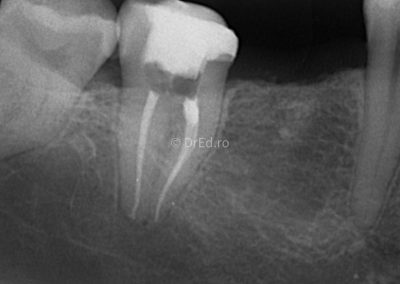

Galerie

Toate imaginile, fotografiile și radiografiile publicate pe acest site sunt protejate prin drepturi de autor și constituie proprietatea exclusivă a Dred.ro.

Aceste materiale sunt furnizate exclusiv în scop informativ și educațional și nu conțin date cu caracter personal sau informații care permit identificarea pacienților, în concordanță cu legislația privind protecția datelor cu caracter personal și GDPR.

Reproducerea, copierea, distribuirea, publicarea, transmiterea, modificarea sau orice altă utilizare, integrală ori parțială, a acestor materiale, în orice formă și prin orice mijloace, fără consimțământul prealabil scris al titularului drepturilor, este strict interzisă și poate atrage răspunderea civilă și/sau penală, în condițiile legii aplicabile privind drepturile de autor și protecția proprietății intelectuale.